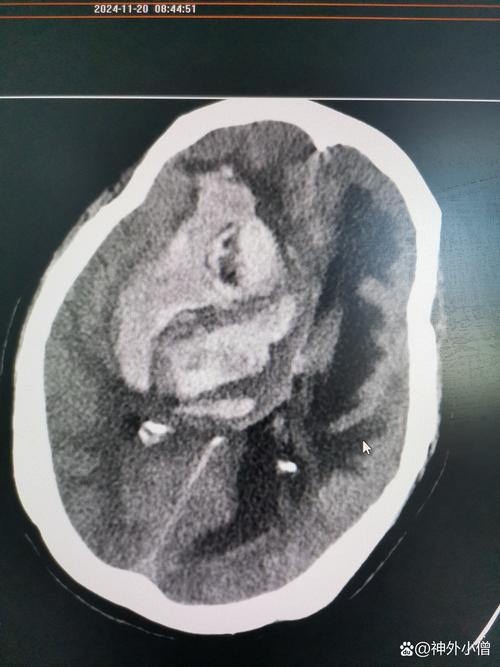

当这几个词组合在一起时,描述的是一次极其凶险的脑卒中(中风)事件,并且病情已经发展到非常危重的阶段,可以把它想象成大脑这个“精密仪器”内部发生了三重灾难:

- 脑梗 (缺血性损伤):大脑某条血管堵塞了,导致一部分脑组织因为缺血缺氧而开始坏死。

- 出血 (破坏性损伤):在缺血区域,或者因为其他原因(如高血压导致血管破裂),血管破裂了,血液流到了大脑不应该有血液的地方,形成血肿,直接压迫和破坏周围的脑组织。

- 积液与脑干变形 (灾难性后果):

- 积液:血液和坏死的脑组织会像“垃圾”一样,刺激大脑产生大量的脑脊液来“冲洗”和包裹这些有害物质,导致颅内压力急剧升高,血肿本身也会占据空间。

- 脑干变形:颅腔是一个封闭的空间,里面的压力急剧增高后,会把整个大脑向压力最低的地方——颅底的枕骨大孔挤压。脑干是连接大脑和脊髓的生命中枢,控制着呼吸、心跳、血压等所有基本生命活动,当它被挤压、变形、移位时,意味着生命中枢受到了直接的、致命的威胁。

“脑梗出血积液脑干变形”是神经科最危重的急症之一,它意味着大脑经历了缺血、出血、水肿三重打击,并且最关键的生命中枢——脑干,已经因为颅内压过高而受到致命性压迫。